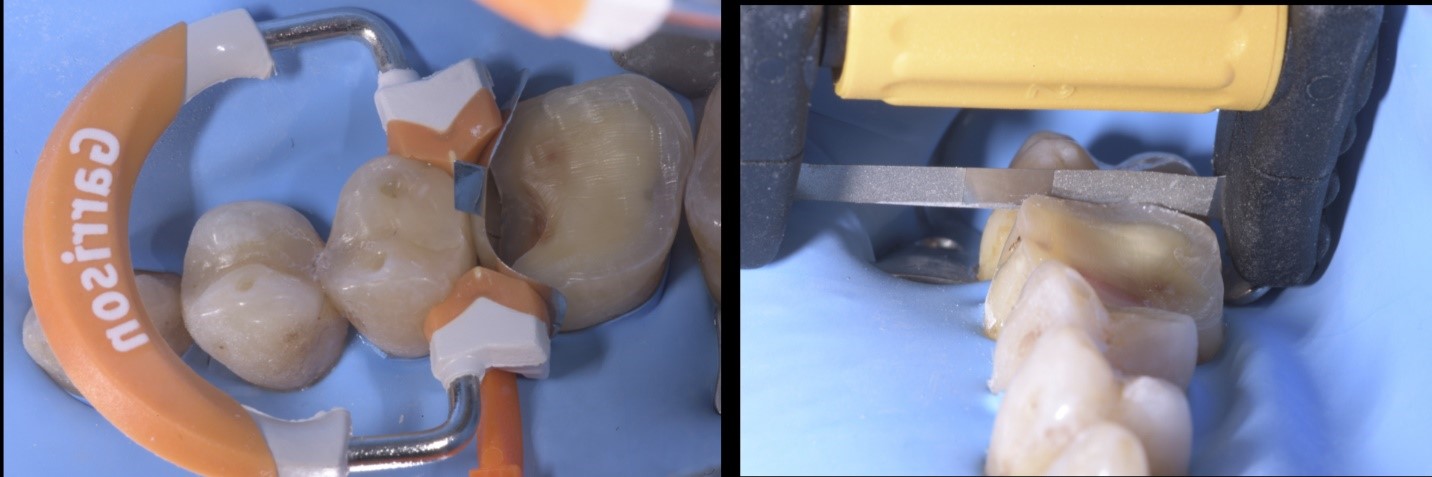

Fig. 4a e 4b

Gli elementi dentali coinvolti da lesioni cariose vengono precedentemente restaurati con materiale composito, mediante l’utilizzo di anelli e matrici Garrison Dental Composi-Tight 3D-Fusion.

L’apertura degli spazi interprossimali in maniera minimamente invasiva è agevolata dall’uso delle strip abrasive Garrison Dental FitSrip, montate su apposito manico di supporto.